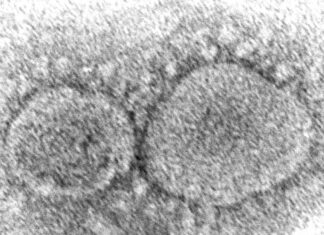

New COVID-19 Vaccine for the Fall Approved by the Federal Drug Administration

The summer surge of COVID-19 cases throughout Philadelphia and the country, making a lot of people sick and affecting back-to-school plans and activities. By...

Nueva vacuna COVID-19 para el otoño aprobada por la Administración Federal de Medicamentos

El aumento veraniego de casos de COVID-19 en Filadelfia y el país, que enfermó a muchas personas y afectó los planes y actividades de...